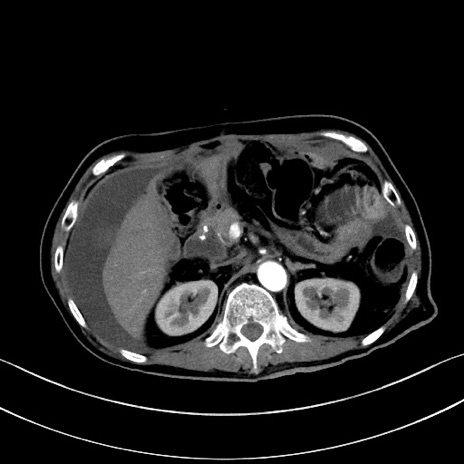

症例28(横断像)

【症例】60歳代男性

【主訴】嘔吐

【現病歴】胃癌にて胃全摘後。食思不振が悪化し、夜中に嘔吐することがある。

【既往歴】胃癌、胃全摘、脾摘、胆摘後

【データ】WBC 5900、CRP 10.56